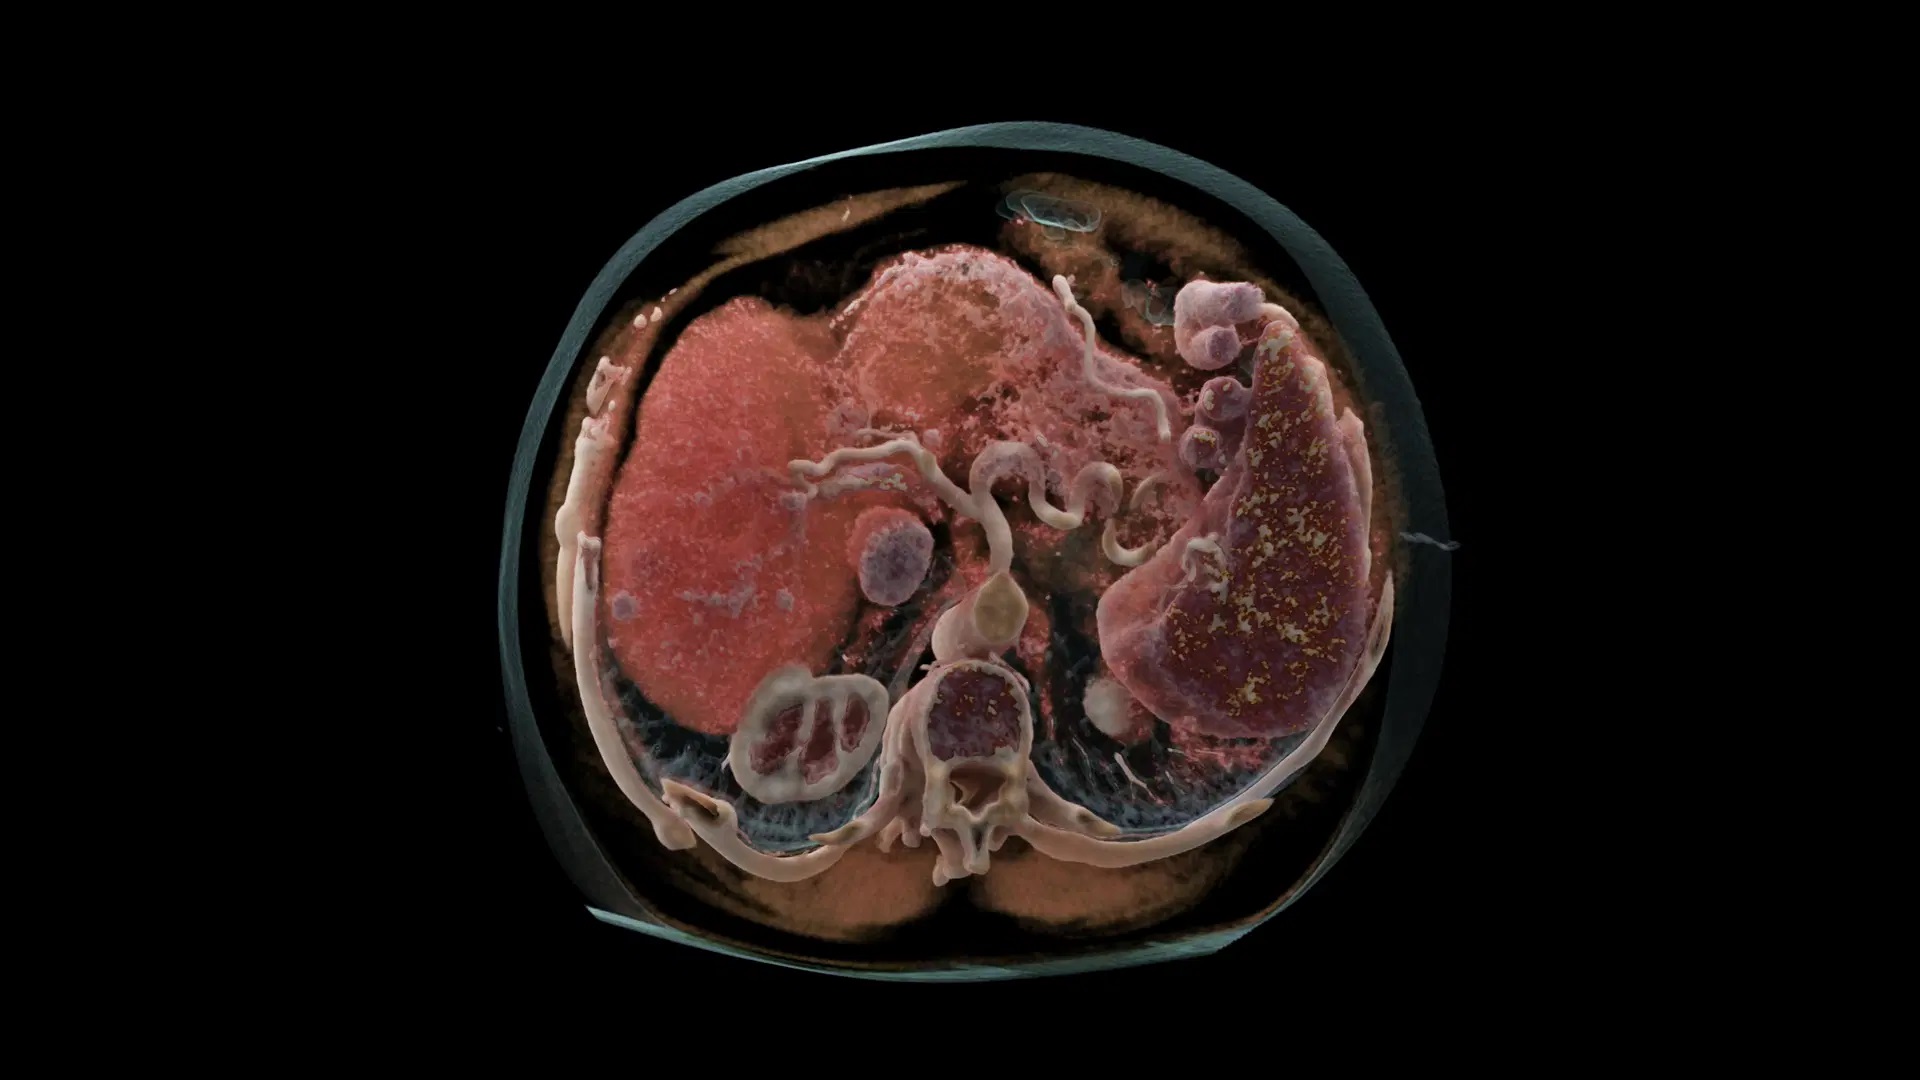

Met een rotatiesnelheid van 0,25 seconden, twee unieke Vectron-röntgenbuizen en twee nieuwste generatie photon-counting detectoren (Dual Source) is de Naeotom Alpha van Siemens Healthineers niet alleen het eerste photon-counting CT-systeem op de markt, maar ook een zeer krachtige, snelle en nauwkeurige CT-scanner. De technische complexiteit betekent geen grotere complexiteit voor de gebruiker, dankzij myExam Companion van Siemens. De klinische beelden bevatten meer informatie dan ooit tevoren voor nauwkeurige diagnose, follow-up en behandeling.

De innovatieve photon-counting detector vormt het hart van de CT-scanner, waar meer dan 15 jaar aan is gewerkt. Met name bij de verwerking van informatie ligt PCCT ver voor op conventionele technieken. Conventionele CT-detectoren zetten de röntgenstralen eerst om in zichtbaar licht om vervolgens om te zetten in een elektrisch signaal. In de tussenstap – ‘omzetten naar zichtbaar licht’ – gaat belangrijke informatie verloren die het zien van contrasten en details vermindert. De PCCT-detector zet de röntgenstralen direct om in een elektrisch signaal waardoor er geen informatieverlies optreedt. Dat betekent dus een beter contrast en meer details in de beelden met tegelijkertijd een lagere patiëntendosis.

Door de directe en snellere informatieverwerking is de stralingsdosis tot wel 45% lager bij scans met ultrahoge resolutie (UHR) in vergelijking met conventionele CT-detectoren met een UHR-kamfilter. Door de lagere stralingsdosis kunnen steeds terugkerende onderzoeken (follow-ups) of wellicht preventief scannen, zoals bijvoorbeeld longkankerscreening met CT, routinematig beschikbaar worden voor grotere groepen patiënten. De hoge resolutie maakt ook kleine structuren zichtbaar, waardoor de klinische besluitvorming naar een nieuw niveau van vertrouwen wordt getild.

De klinische gebieden van cardiale beeldvorming, oncologie en pulmonologie stellen allemaal hun eigen unieke eisen aan medische beelden. Bij cardiale beeldvorming gaat het om het vastleggen van het hart terwijl het beweegt, wat dus snelheid vereist. De Naeotom Alpha levert snelheid dankzij het Dual Source ontwerp en profiteert van werkelijke spectrale informatie en hoge resolutie voor het verwijderen van obstructies veroorzaakt door verkalkingen. Hierdoor is diagnostische beoordeling veel beter mogelijk, zelfs bij patiënten met aanzienlijke hoeveelheden kalk in de vaten. De hoge nauwkeurigheid is ook gunstig in de oncologie, waar betrouwbare en consistente evaluatie van het ziekteverloop belangrijk is. In de pulmonologie moeten de beelden alle zinvolle antwoorden bevatten in zo weinig mogelijk scans om vertragingen in de behandeling te voorkomen. Aan die behoeften voldoen de functies van Naeotom Alpha of overtreffen die.